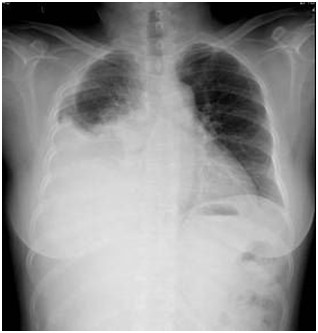

05卷-3.老年女性,60岁,咳嗽、咳痰伴气促3小时入院,胸片提示(本题满分2.00分)

A.气胸

B.间质性肺炎

C.病毒性肺炎

D.胸腔积液

本题答案:D

题目解析:

【该题针对“ X线-胸腔积液 ”知识点进行考核】